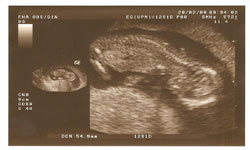

SEMANA 12 . TÚ... Tú útero es demasiado grande para permanecer en tu pelvis y empuja por encima de tu hueso pélvico. Y TÚ BEBE... Pesa unos 14g y mide 8cm. En la eco puedes ver cómo mueve manos y piernas. |